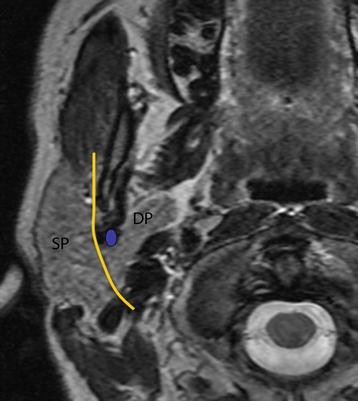

The facial nerve (the labyrinthine segment) is the seventh cranial nerve, or simply CN VII . It emerges from the pons of the brainstem, controls the muscles of facial expression . . .

The first extracranial branch to arise is the posterior auricular nerve . The first motor branch arises within the facial canal; the nerve to stapedius . [start-clinical] .

The branches of the nerve which are responsible for the various facial expressions are: 1 . Temporal branch 2 . Zygomatic branch 3 . Cervical branch 4 . Buccal branch 5 . Marginal mandibular branch .

Posterior auricular nerve, branch to posterior digastric belly, branch to stylohyoid muscle, temporal branch, zygomatic branch, buccal branch, marginal mandibular branch, cervical branch .

Branches facial nerve . Anatomy , cranial nerve , neurology , notes , practical notes . Stylohyoid supplies stylohyoid muscle . Branches in the Parotid region Temporofacial branch .